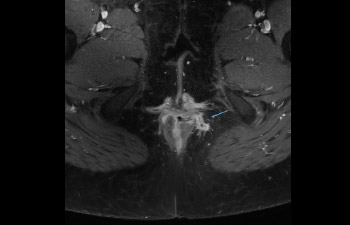

Pelvis with fistula